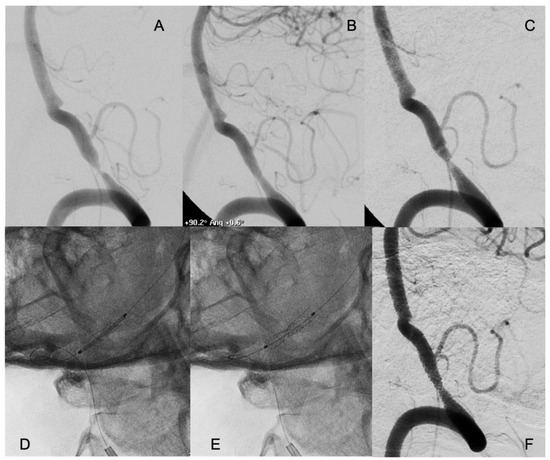

Restenosis (≥50%) at median radiological follow-up of 12 months was observed in 4 patients (11.1%): 2 patients were treated with self-expanding stents and 2 patients with bare-metal stents). All four patients had symptomatic restenosis. Two of these restenoses required endovascular re-treatment; 1 patient was re-treated with balloon angioplasty, and 1 patient with drug-eluting stent (Figure 2).

Figure 2. A patient who suffered several drop attacks due to a stenosis of the right vertebral artery with concomitant occlusion of the left (A). The patient underwent endovascular treatment with placement of a coronary balloon-expandable stent, which resolved the stenosis and relieved the symptoms (B). Six months later, symptoms relapsed, and an in-stent restenosis was diagnosed (C). An everolimus-eluting coronary balloon-expandable stent was placed, covering the bare metal previously placed (D,E) with complete resolution of the in-stent restenosis (F). The patient had no new symptoms in the follow-up, with persistence of the patency of the treated artery.